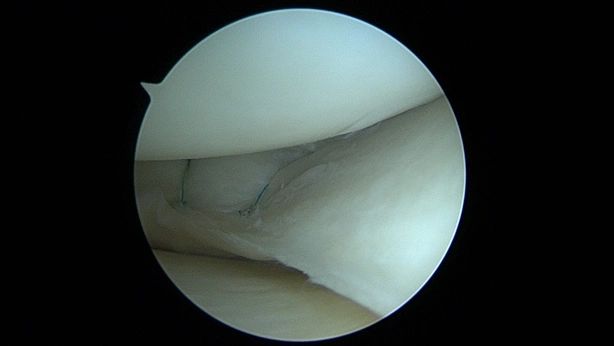

- Meniscus Surgery

- Meniscus Surgery 2